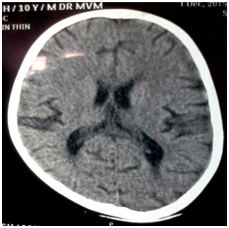

A 10-year-old male, hailing from Ratnagiri district of Maharashtra, India was admitted to the hospital, with history of fever accompanied by fronto-parietal headache and body ache for 1 month. He also complained of productive cough with expectoration and breathlessness for 15 days. The patient was diagnosed with Human Immunodeficiency Virus (HIV) infection 1 month before admission, following which he was started on anti-retroviral therapy (ART). His mother was diagnosed with HIV infection 3 years ago and was started on ART. His father was also diagnosed with the same 2 months back, but was not on treatment. The patient had a 13 year old sibling who was HIV seronegative. Local examination revealed gross emaciation, small subcutaneous nodules about 3-5 mm in diameter over face (Figure 1) and palpable post auricular & bilateral medial axillary lymph nodes. Neurological examination did not reveal any meningeal signs apart from brisk plantar reflexes. Haematological parameters showed macrocytic anaemia with anisocytosis on peripheral blood smear, gross leucopenia (1900 cells/mm3) and mildly elevated Erythrocyte Sedimentation Rate (ESR 35mm at 1 hour). Serum creatinine was high (1.2 mg/dl). He had hypokalemia and severe Vitamin B12 deficiency. CD4 count was markedly reduced (8 cells/mm3). Chest X-Ray revealed diffuse infiltration in the right middle and lower lobes (Figure 2). Ultrasonography (USG) of abdomen revealed multiple, non-necrotic retroperitoneal lymphadenopathy. Computed tomography (CT) scan of brain showed age unrelated atrophy (Figure 3).

Figure 3 CT scan of brain showing age unrelated atrophy.